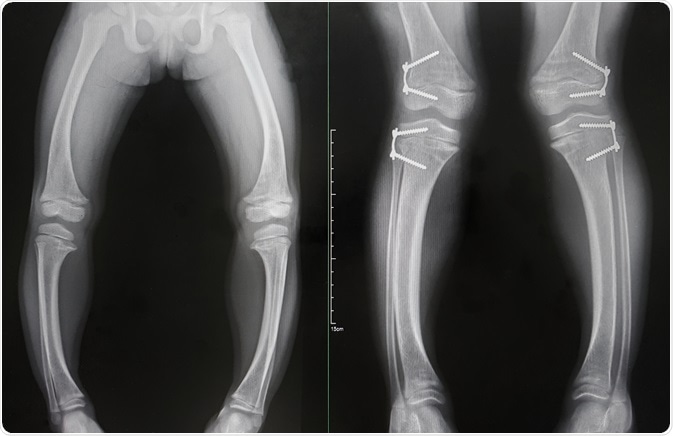

Rickets was initially reported in the mid-1600s when children who lived in polluted industrialized cities of northern Europe developed a severe bone-forming disease characterized by deformities and growth retardation. Glisson and his colleagues described typical findings of bone deformity with the curving of the legs.

ricketsRickets. Image Credit: Bunsinth-Nan-Pua / Shutterstock.com